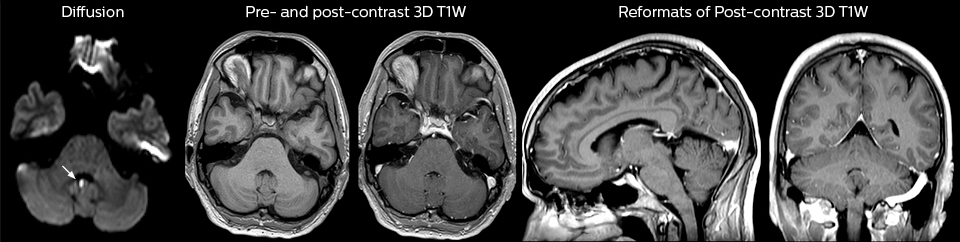

This patient presented with headache that was worse with neck flexion and we see a Chiari 1 malformation with low-lying cerebellar tonsils as well as some degenerative cervical thrombolytic change.

A range of protocol sheets was developed to help ensure that referring physicians order the most appropriate MRI exam. The optimized MRI protocols also include 3D contrast-enhanced imaging, allowing neurosurgeons to comfortably use the isotropic data in the operating room while performing stereotaxic surgery.